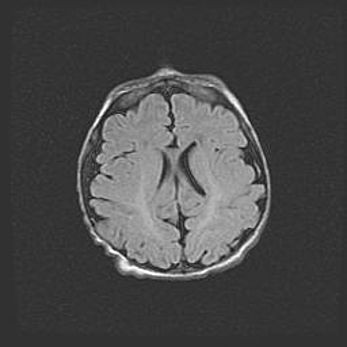

Наружная гидроцефалия с возможной атрофией височных областей.

Возраст: 28 дней

Вес: 3670 г

Пол: мужской

Окружность головы: 38 см

Срок гестации: 40 недель

Гидроцефалия головного мозга у новорожденных – это заболевание, которое характеризуется скоплением избыточного количества спинномозговой жидкости в желудочковой системе головного мозга в результате затруднения её перемещения от места выработки к месту поглощения в кровеносную систему или вследствие нарушения абсорбции. При открытой наружной форме гидроцефалии у новорожденных расширяются и переполняются субарахноидные пространства.

При нормотензивных  формах,  которые,  как  правило,  являются  следствием  перенесенных ишемических  повреждений  паренхимы  мозга,  возможно  сочетание микроцефалии  с нормотензивной гидроцефалией. В основе данных изменений лежит атрофия больших полушарий с преимущественной  локализацией  в  лобно-височных  областях.